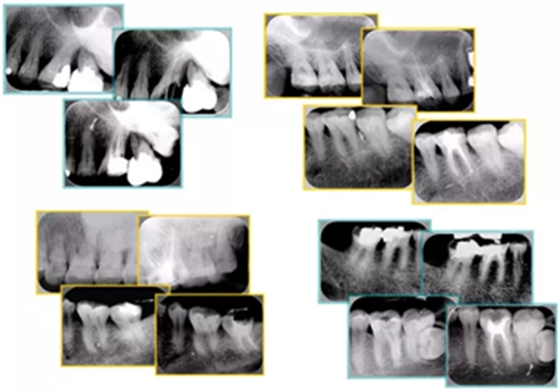

6. 術(shù)后 X 線片

術(shù)后 X 線片用來評定根管充填 長度、致密度(管壁清晰、側(cè)枝)等指標(biāo)。

圖為根管充填術(shù)后 X 線片。圖中可見,根管充填較好。右下圖有白色小點(diǎn),為側(cè)方加壓導(dǎo)致糊劑擠出所致,表明根管充填比較致密。

致密、恰到好處的充填可去除干凈根管里感染灶,機(jī)體逐漸恢復(fù)。

多根牙時候需進(jìn)行偏移投照,正位投照無法說明具體哪根牙根管充填效果。